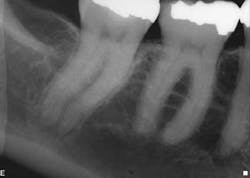

When the anatomy is more complicated than can be predictably treated with WaveOne, but not so irregular as to require all of the files of Vortex Blue, is there another option? It is in these clinical situations that ProTaper Next® (Dentsply Tulsa Dental Specialties) becomes the best file system (Figs. 5 and 6). The rectangular but off-center cross-section creates the illusion that the canal is slightly larger than it is because the alternating contact points of the file prevent the feeling of the file getting locked into the canal space. This added space along the file results in additional room for debris removal, and in spite of this design, there is no appreciable loss of cutting efficiency. When using ProTaper Next files to create the final root canal shape, two or three instruments will be used.

Fig. 5: With a crown in place, it can be difficult to determine the size of the pulp chamber. However, at the level of the roots, the canals in tooth No. 3 look to have calcified compared to the neighboring teeth.

Fig. 6: After locating the canals and following the glide path to the root ends with hand files, two ProTaper Next files were used in each root canal to create the final shape.